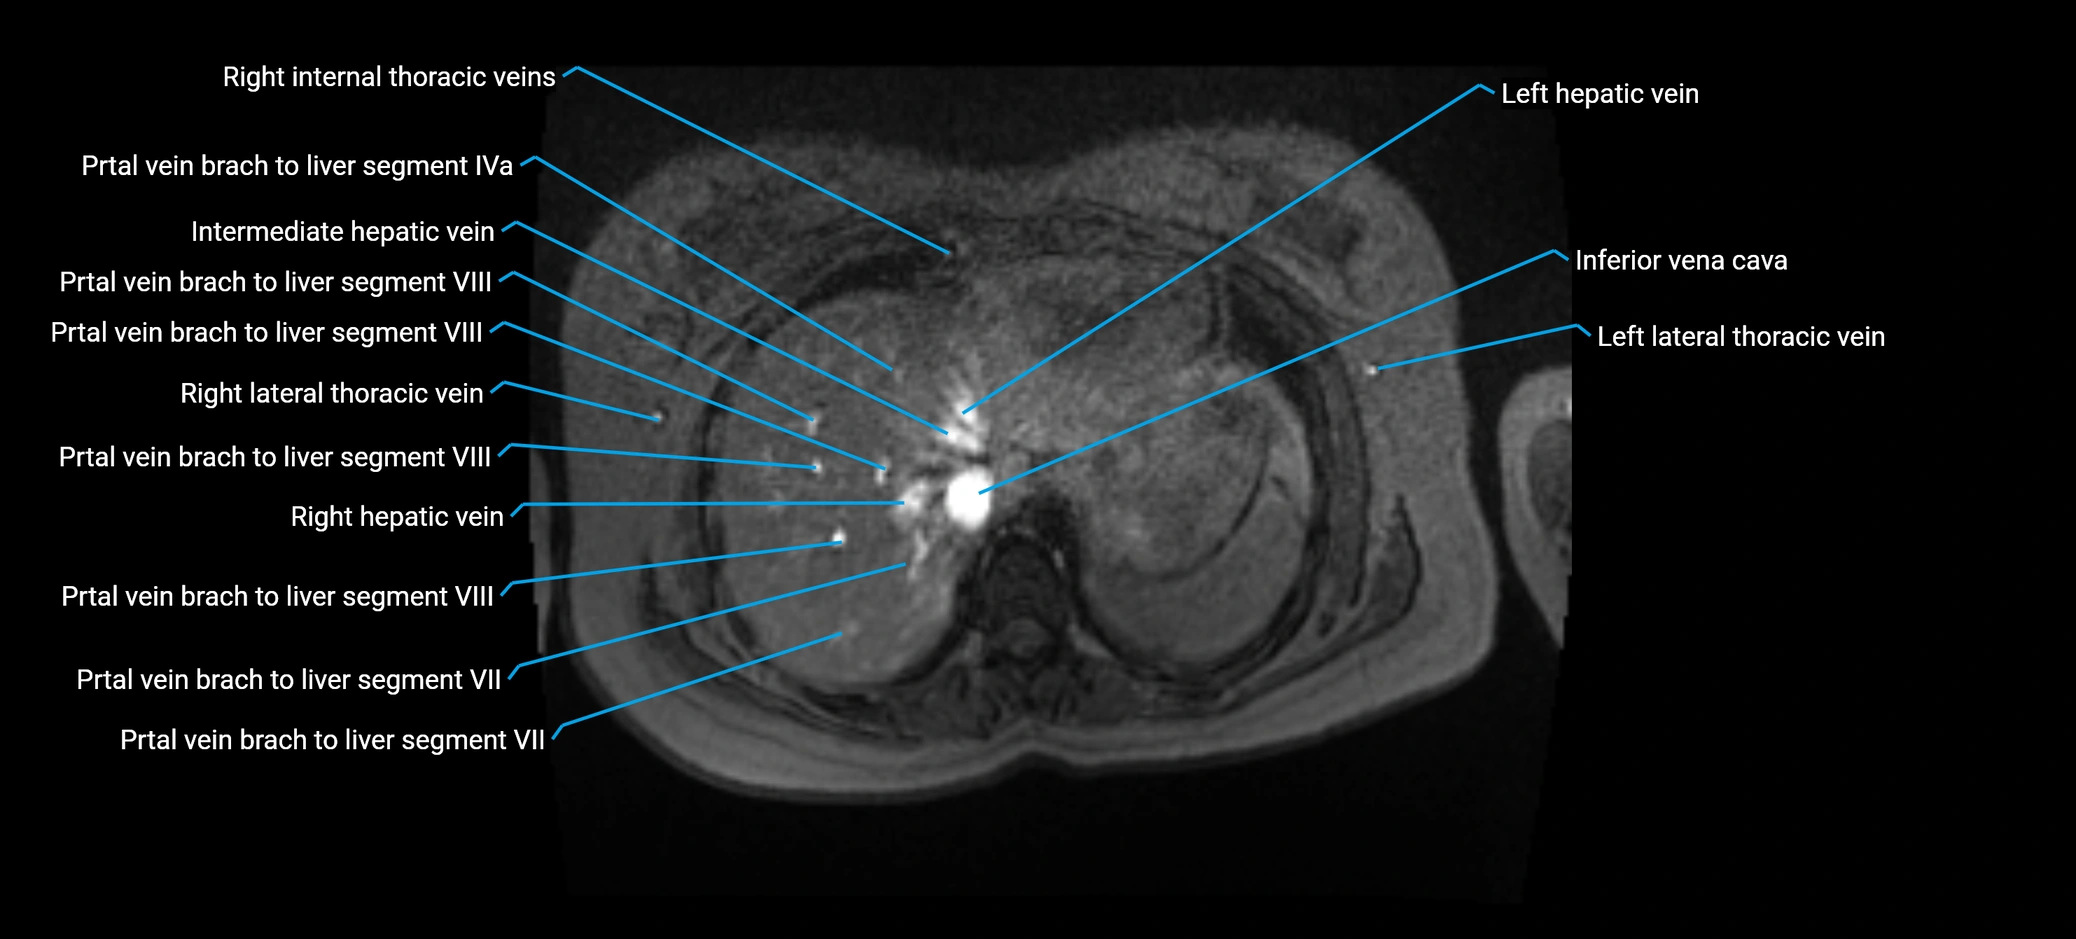

MRV TOF (Time-of-Flight MR Venography):

• Appears as a bright, high-signal vascular channel representing flowing blood

• Clearly shows branching pattern of right portal vein into anterior and posterior branches

• Best in coronal or axial reconstructions for segmental mapping

• No need for contrast, relies on flow-related enhancement